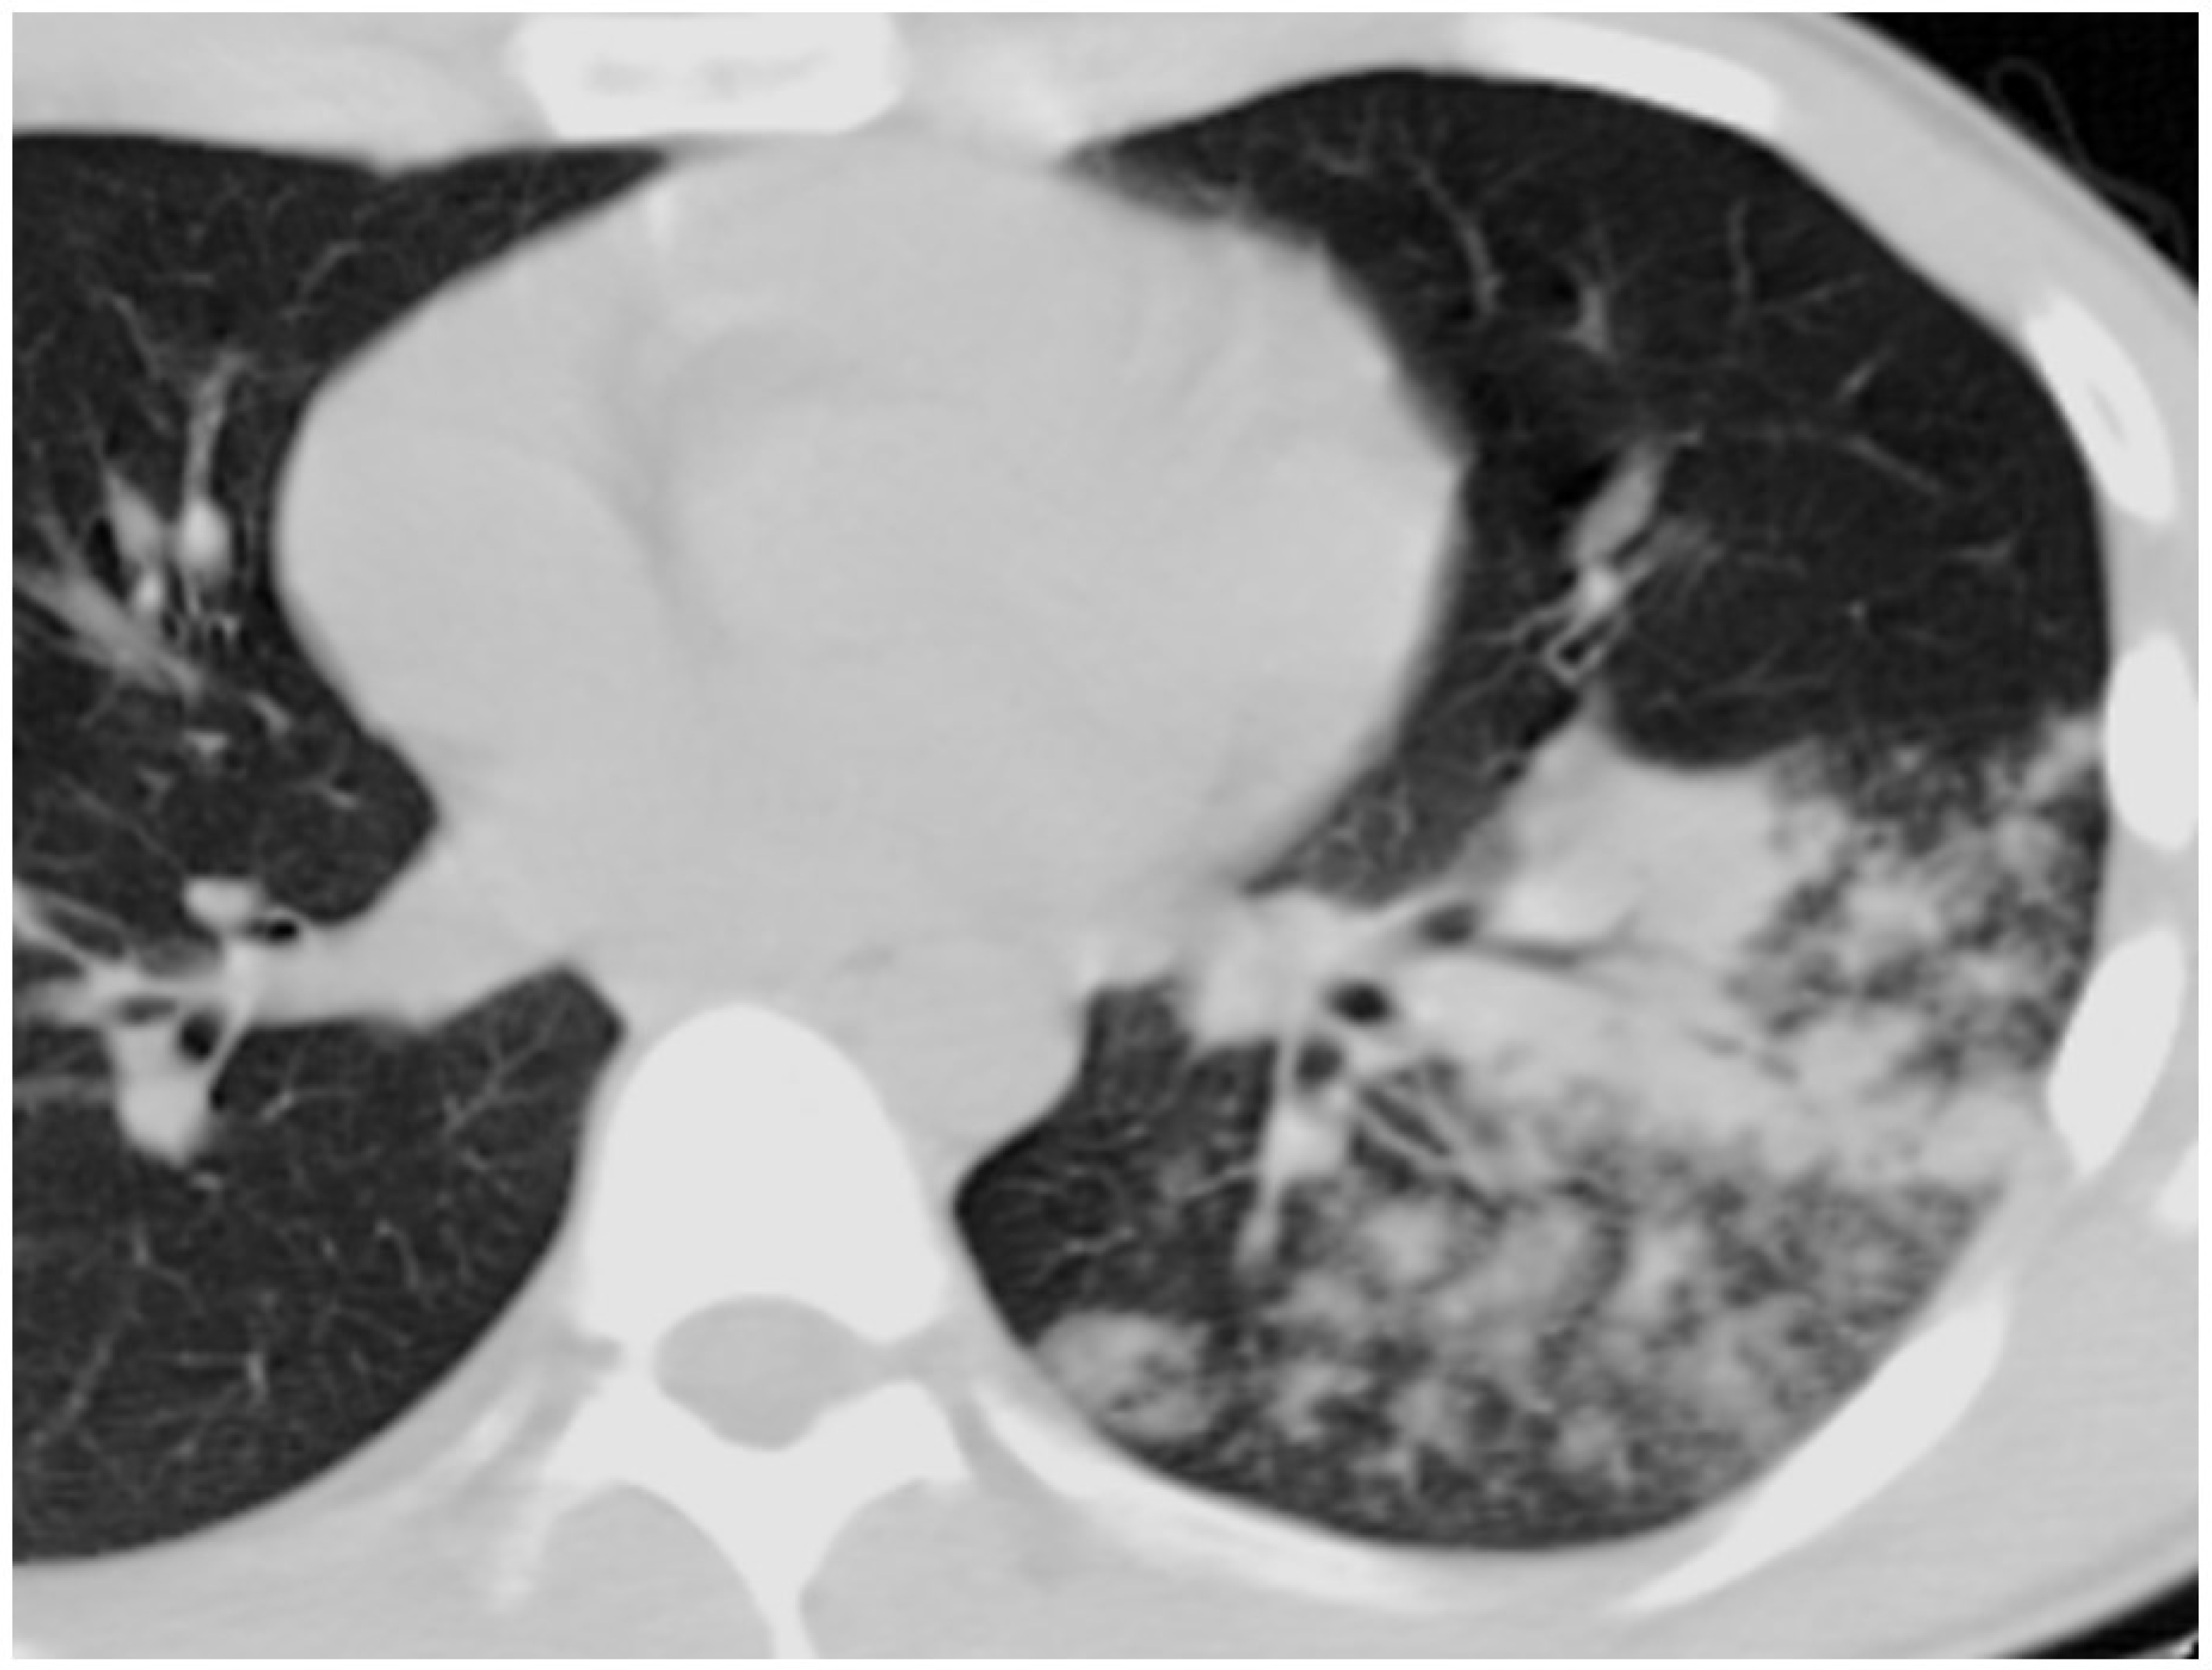

- D’Angelo, A.; De Simone, C.; Pagnottella, M.; Rossi, S.; Pepe, R.; Ruggieri, G.; Cocco, G.; Schiavone, C. A Case of Legionella pneumophila Evaluated with CT and Ultrasound. J. Ultrasound 2017, 20, 243–245. [Google Scholar] [CrossRef] [PubMed]

- Nakanishi, M.; Shiroshita, A.; Nakashima, K.; Takeshita, M.; Kiguchi, T.; Yamada, H. Clinical and Computed Tomographic Features of Legionella Pneumonia with Negative Urine Antigen Test Results. Respir. Investig. 2021, 59, 204–211. [Google Scholar] [CrossRef] [PubMed]

- Kim, K.W.; Goo, J.M.; Lee, H.J.; Lee, H.Y.; Park, C.M.; Lee, C.H.; Im, J.-G. Chest Computed Tomographic Findings and Clinical Features of Legionella Pneumonia. J. Comput. Assist. Tomogr. 2007, 31, 950–955. [Google Scholar] [CrossRef]